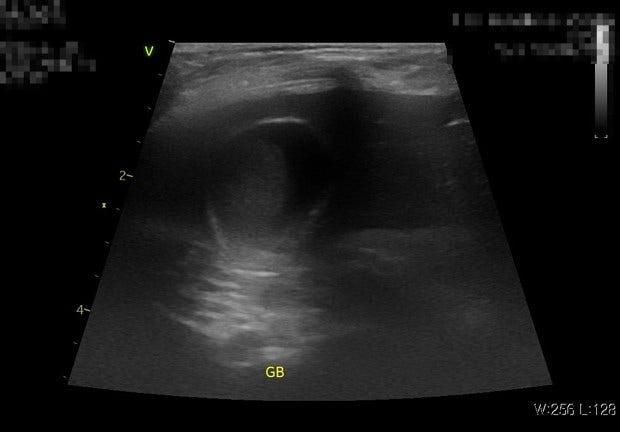

췌장염 때문인지 담낭 때문인지 비명을 지르는데요.. 낫게 할수있는 방법이 없을까요? 애가 안절부절 못하면서 난생처음들어보는 비명을 지르는데 치

췌장염 때문인지 담낭 때문인지 비명을 지르는데요.. 낫게 할수있는 방법이 없을까요?

애가 안절부절 못하면서 난생처음들어보는 비명을 지르는데

치료약은 없는걸까요? 낫게할수있는 방법이 없을까요?

병원만 3-4곳을 다녀와도 나아지긴커녕 오히려 증상들만 더 추가되고 악화만 되고있습니다

혀를 낼름낼름 소처럼 입맛을 다시는 오심 증상과 기지개 켜는 횟수가 점점 많아지고 복명음은 날이 갈수록 커져만 갑니다

담낭도 어떤 수의사분은 괜찮다하고 어떤 수의사분은 중증도라고 그러고

어떤분은 우루사+르와콜 먹이라고하고 어떤분은 우루사 먹이라고하고

어떤분은 담낭의 찐득임을 알수없기 때문에 우루사 복용시 막힐수가 있어서 보호자 선택사항이라하고

또 췌장 같은 경우는 어떤 수의사분은 급성이라하고 어떤분은 만성이라고하고 어떤분은 만성의급성화라고어느분은 췌장염이 아니라고하는분도 있고 다 달라서 진심으로 무슨 장단에 맞춰야할지를 모르겠고

누구 말을 따라야 증상이 호전이 될수가 있는건지 감도 안옵니다. 작년 11월부터 병원만 3-4곳 다녔는데 나아질 기미가 안보이네요